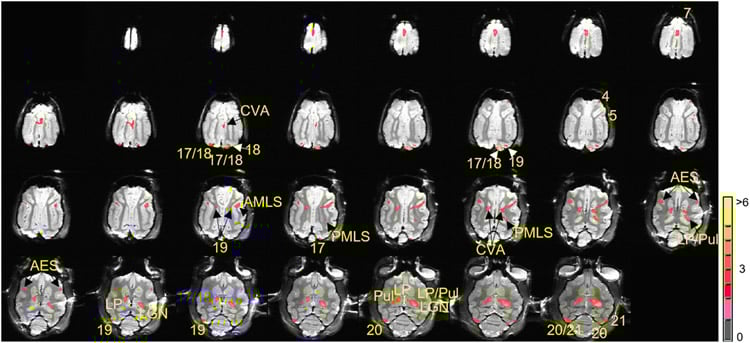

Image shows brain images.

FeaturedNeurologyNeuroscience

·October 6, 2017·6 min read

Machine Learning Used to Automatically Identify Brain Tumors

Researchers from UT Austin utilize deep learning and supercomputing to help identify brain tumors.

Read More